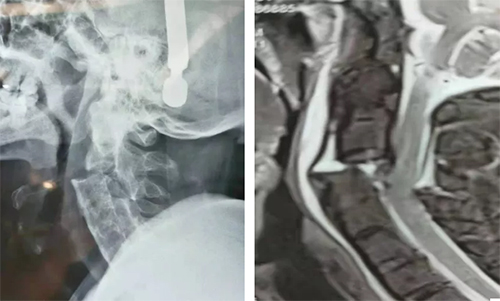

罹患强直性脊柱炎多年的杨先生近期因车祸导致头颈部疼痛、活动受限。当地检查示,C2/3骨折脱位,强直性脊柱炎,颈髓损伤,蛛网膜下腔出血,颌面部多发骨折并软组织损伤。由于治疗风险高、护理难度大,患者连夜转运到我院中心院区创伤二科(创伤急诊外科)病房就医。

经牵引部分复位后,科室医生充分讨论排除手术禁忌,制定合理的手术方案以及完善的应急预案。麻醉手术科高度重视,麻醉师王晓艳和崔喆,手术室护士刘磊和彭雪莹与王甫手术团队密切配合,对患者行极度屈曲位、清醒状态下、经口插管,清醒翻身,并进行特殊体位调整等高危操作。王甫、韩勇、路庆森组成的手术团队,克服了广泛结缔组织病变出血多,颈椎不稳,骨质松脆,缺乏解剖标志等困难,为患者施行了“颈椎椎弓根钉植入+颈椎复位+长节段枕颈融合术”。手术全程精细操作,每一步都细致精确,术中共出血300ml,未输血。患者术后颈部疼痛不稳症状明显缓解,四肢感觉运动正常。